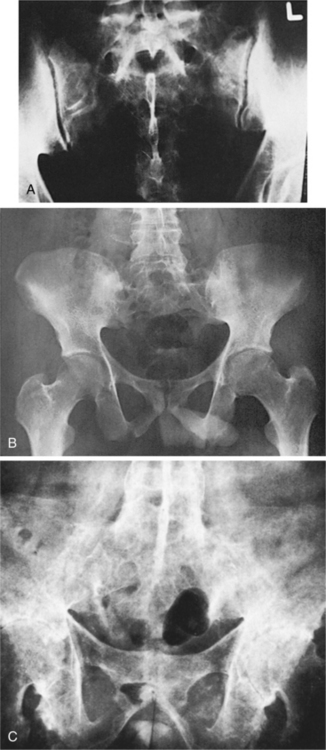

Disruption of this ligamentous-osseous junction results, and reactive bone formation occurs as part of the repair process. Cartilage of the sacroiliac joints may also be involved (Fig. 27-19). The replacement of inflamed cartilaginous structures by bone contributes to progressive ossification with bony growth between the vertebrae, leading to a fused, rigid, or bamboo spine, characteristic of end-stage disease (see Fig. 27-20).

Figure 27-19 Progression of ankylosing spondylitis of the sacroiliac joints. A, Normal sacroiliac joints. B, Fusion of sacroiliac joint spaces; the sclerosis has resorbed, and there is slight narrowing of the left hip joint. C, Advanced ankylosing spondylitis with generalized osteoporosis and fusion of the spinous process, intervertebral disks, sacroiliac joints, and symphysis pubis. The entire skeletal unit has been transformed into one continuous osseous mass. (A, from Magee D: Orthopedic physical assessment, ed 2, Philadelphia, 1992, Saunders, p 329. B, from Rothman RH, Simeone FA: The spine, Philadelphia, 1982, Saunders, p 921. C, from Bullough PG: Orthopaedic pathology, ed 3, London, 1997, Mosby-Wolfe, p 300.)